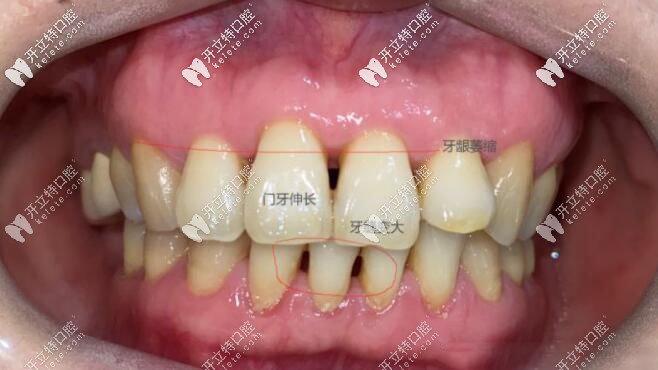

現(xiàn)在我的牙齒缺失少則也有五六年了, 為什么現(xiàn)在才種,因?yàn)楝F(xiàn)在的我30多歲面頰已經(jīng)凹陷,牙齦也有萎縮,鄰牙也已經(jīng)開始傾斜, 主要是門牙伸長(zhǎng)已經(jīng)影響我的美觀了。